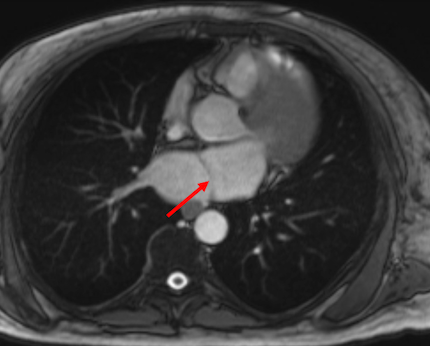

Case Presentation: A 47-year-old male with a history of heart failure with reduced ejection fraction, hypertension, and type 2 diabetes mellitus presented with acute, left-sided weakness. On arrival, his blood pressure was markedly elevated at 206/110 mmHg, and capillary blood glucose exceeded 500 mg/dL. EKG demonstrated atrial fibrillation (AF). Brain MRI confirmed multifocal acute infarcts, consistent with an embolic pattern. Transthoracic echocardiogram detected a severely dilated left atrium with a fibromuscular ridge; subsequent cardiac MRI confirmed a fenestrated membrane dividing the left atrium, consistent with a diagnosis of Cor Triatriatum Sinister (CTS), as well as asymmetric severe septal hypertrophy with late gadolinium enhancement raising concern for hypertrophic cardiomyopathy (HCM). The patient’s weakness improved, and he was started on apixaban 5 mg twice daily for embolic stroke prevention. He opted for a wearable cardioverter-defibrillator rather than pursuing inpatient ICD placement or catheter ablation. He was discharged in stable condition with general cardiology, electrophysiology, and adult congenital heart disease follow-up.